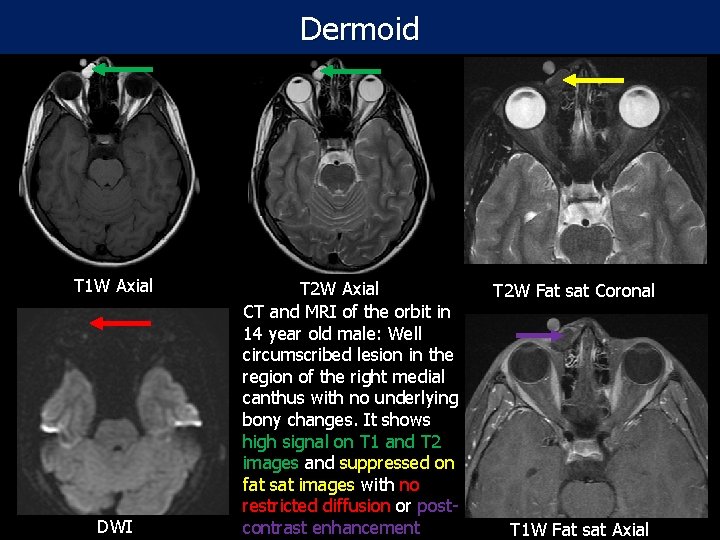

Dermoid T 1 W Axial DWI T 2 W Axial CT and MRI of the orbit in 14 year old male: Well circumscribed lesion in the region of the right medial canthus with no underlying bony changes. It shows high signal on T 1 and T 2 images and suppressed on fat sat images with no restricted diffusion or postcontrast enhancement T 2 W Fat sat Coronal T 1 W Fat sat Axial